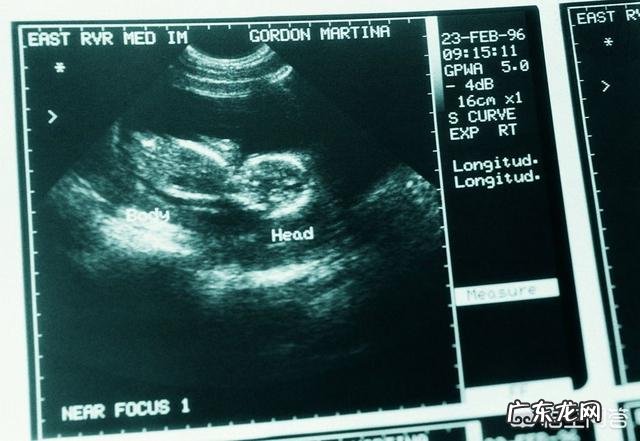

还有一个检查那就是对胎儿性别的鉴别 , 这个在我国属于违法行为 , 国外好像没有对这方面的要求(图片是国外的资料) , 可以对胎儿进行性别鉴别 。临床上鉴别胎儿性别的主要两种途径就是染色体和B超 , 对于B超来讲孕4个月到5个月通过胎儿外生殖器形状来判断胎儿性别还是比较靠谱的 。准确率在90%左右 , 至于那些所谓的女翻男都是B超看错导致的 , 而不是女宝真的可以变为男宝 , 胎儿的性别在生就去时就已经决定了得 。

总结 , 怀孕4个月此时胎儿的外生殖器官已经成形 , 此时看男看女还是比较靠谱的 。祝好孕 , 儿女双全 。